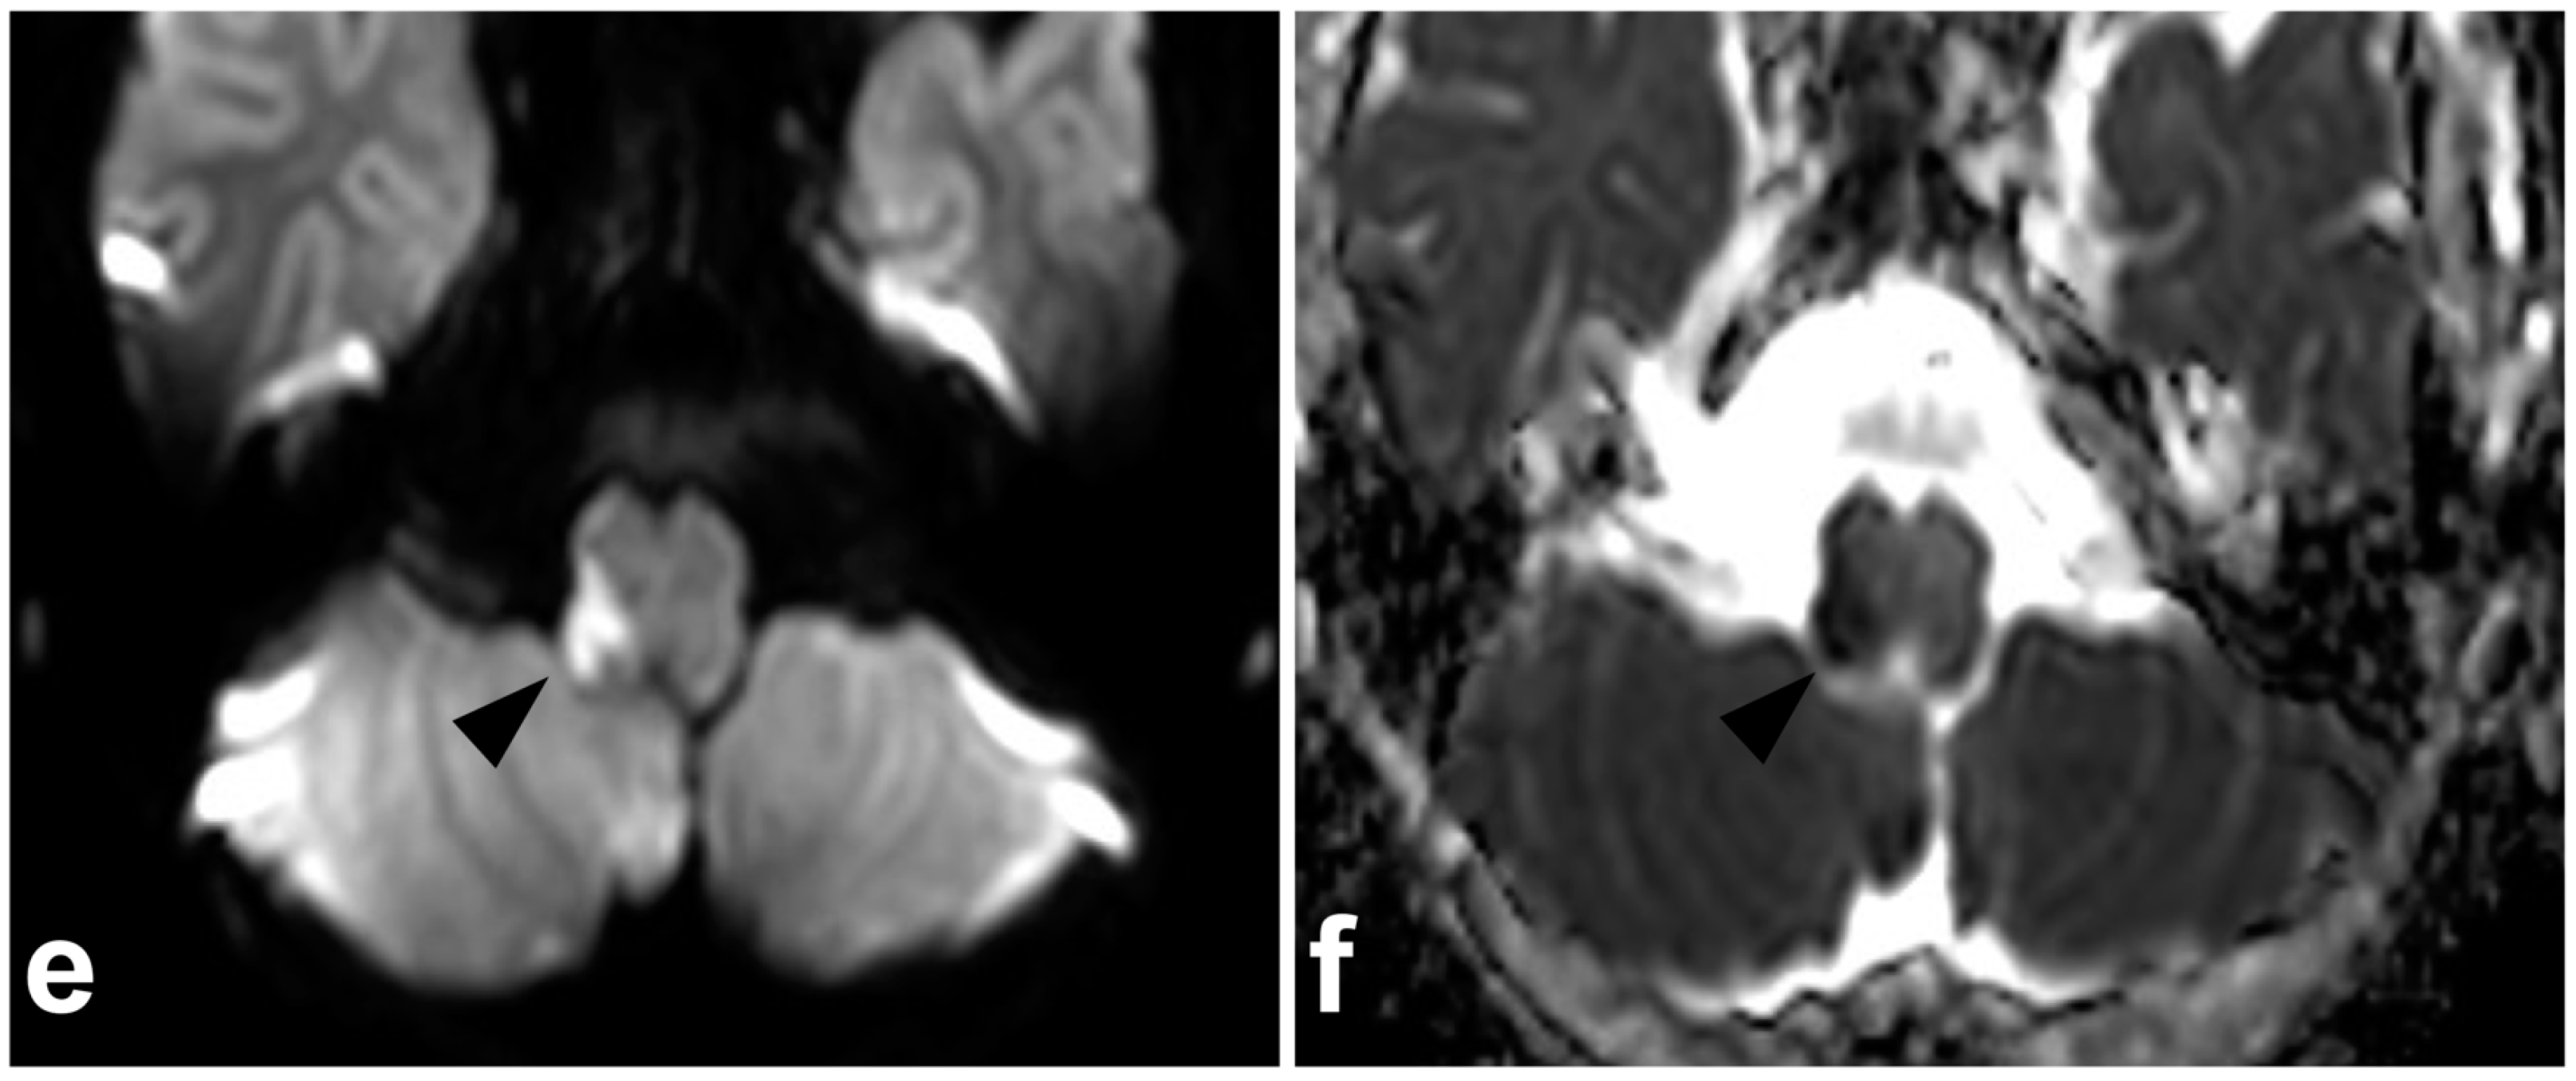

3.2. Chance Fractures

4.2. Posterior Ligament Complex

4.3. Anterior and Posterior Longitudinal Ligaments

5.1. Intervertebral Disc Injuries